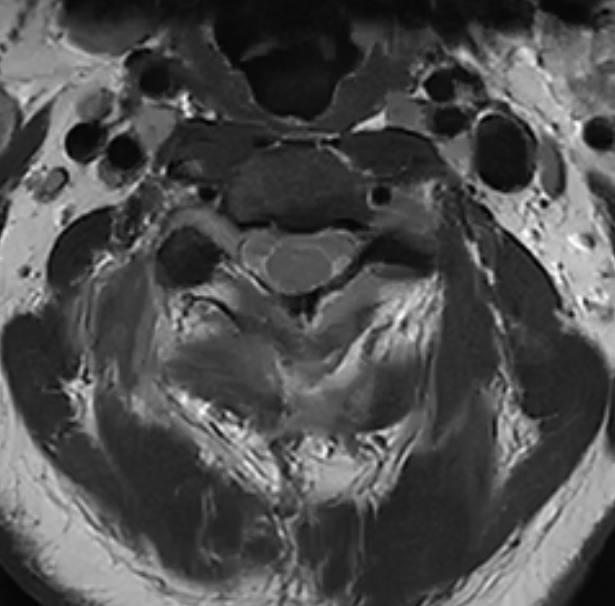

术后MRI平扫

经过充分的术前准备,仇继任及其团队如期为罗先生进行手术。手术过程中发现肿瘤组织与延髓神经组织粘连紧密,手术难度进一步增大。凭借着精湛而熟练手术技巧及默契的团队配合,仇继任在显微镜下仔细分离肿瘤与脊髓神经组织、精确止血。经过2小时的紧张奋战,手术顺利结束。术后在科室全体医护人员的精心护理下,患者右侧下肢疼痛、麻木症状明显缓解。由于术中未破坏关节突关节,脊柱稳定性得到大部分保留,罗先生术后很快便能起床活动,术后1个星期出院,1个月后随访恢复良好。

高位颈椎管内肿瘤,一般是指发生在颈椎的第1到4节段的椎管内肿瘤,这些肿瘤可以包括脊髓髓内的星形细胞瘤、室管膜瘤、脊髓髓外的脊膜瘤、神经鞘瘤等。由于其毗邻延髓,具有特殊解剖生理特点,易并发四肢瘫痪和呼吸功能障碍,在诊断和治疗上存在较大的困难。表现的症状比较严重而突出。部分患者出现走路不稳,肩背部的疼痛、麻木,双上肢的疼痛、麻木;严重的可以出现肢体的瘫痪、心率呼吸减慢,有的患者甚至可能会出现心跳呼吸骤停这样严重的危害。所以高位颈椎的椎管内肿瘤是一种手术难度比较大,手术风险比较高的肿瘤。